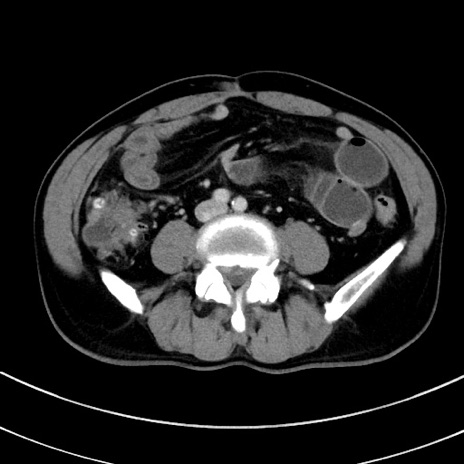

症例8(横断像)

【症例】 60歳代男性

【主訴】 黒色吐物

【現病歴】 4日前から嘔気自覚、2日前の朝食後にも嘔気あり、自分で手で嘔吐反射起こし嘔吐したところ血が混ざっていたため受診。

【既往歴】 5年前汎発性腹膜炎を伴う急性虫垂炎で手術、高血圧、前立腺肥大症、高脂血症

【身体所見】 腹部正中に手術癩痕あり 腹部平坦・軟圧痛なし膨満感あり

【データ】WBC 8400、CRP 4.54